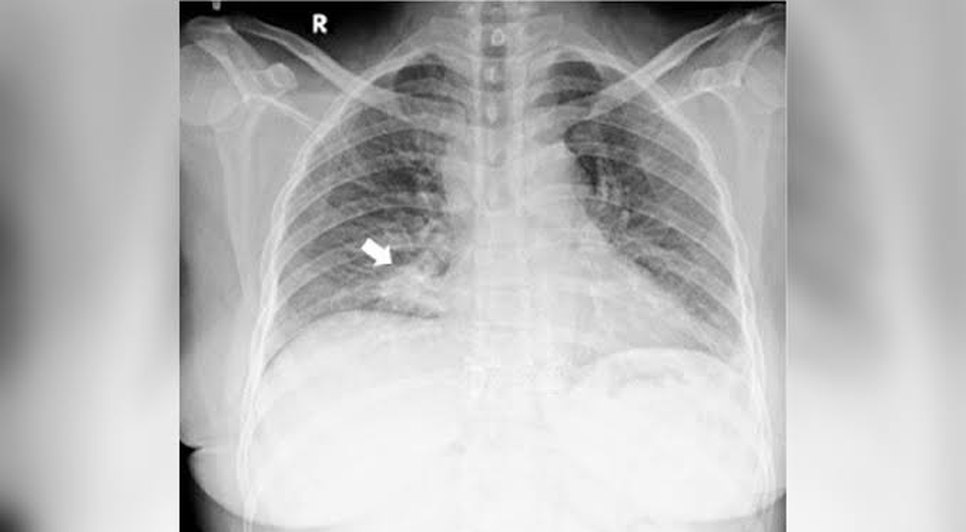

A partir da realização de exames, os médicos notaram uma grande lesão abaixo da retina do olho direito e a mesma lesão, só que menor, no olho esquerdo. Foi então que a equipe colocou a mulher para fazer uma radiografia, que encontrou o nódulo na zona inferior do pulmão direito.

A partir desses exames, outros foram feitos e mais tumores foram encontrados em outros órgãos. A mulher, que não teve seu nome revelado, foi diagnosticada com carcinoma de pulmão e com metástase de coróide (membrana que envolve o olho) em ambos os olhos.